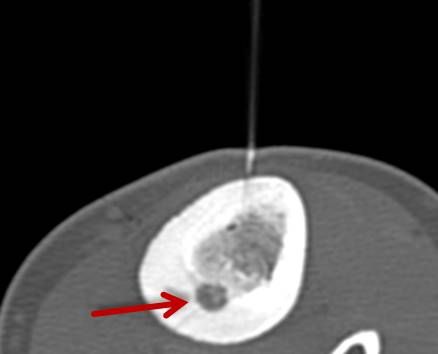

Abbildung: Bei der perkutanen Thermoablation von Lungentumoren werden spezielle Applikatoren unter CT-Bildgebung in den Zieltumor eingebracht. Durch Hitze wird der Tumor dann zerstört.

RFA zur Therapie des Osteoidosteoms

Das Osteoidosteom ist ein gutartiger, jedoch sehr schmerzhafter Knochentumor, der bevorzugt bei jüngeren Patienten auftritt. Die Radiofrequenzablation (RFA) hat sich in den letzten Jahren zu einer zuverlässigen, minimalinvasiven Therapieoption bei der Behandlung des Osteoidosteoms entwickelt und wird seit über 15 Jahren an der Uniklinik Tübingen angewandt.

Abbildung: Osteoidosteom (Pfeil) im Schienbein bei einem jungen Patienten. Unter CT-Bildgebung wird ein spezieller Applikatoren unter CT-Bildgebung in das Osteoidosteom eingebracht. Durch Hitze wird dieses effektiv und dauerhaft zerstört.